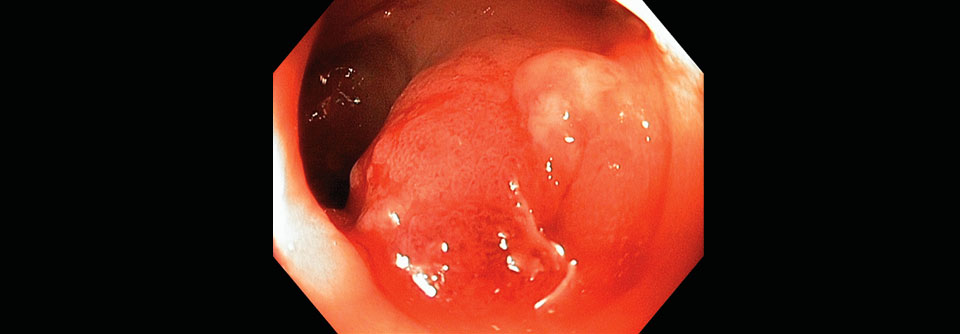

Symptomatik

Bei der komplizierten Divertikulitis ist eine Laparotomie indiziert.